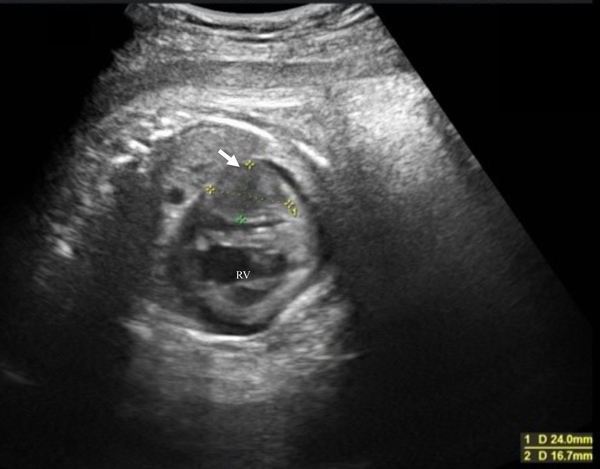

A 37-year-old pregnant woman in the 36th week of gestation (gravida 1, para 0) was transferred to our hospital due to a fetal cardiac mass noted during fetal echocardiography. Her fetal echocardiographic examination showed a large homogeneous, hypoechoic mass (24.0×16.7 mm), occupying the left ventricular cavity almost completely (Fig. 1). Other cardiac abnormalities were not detected. A male neonate was born via uncomplicated vaginal delivery at 36 weeks and 4 days of gestational age, weighing 2,896 g, the 1- and 5 minutes Apgar scores both 8. At birth it is found crying vigorously and spontaneously with good cardiorespiratory adaptation, tone and reactivity appropriate for gestational age. On physical examination, blood pressure was 58/34 mmHg, pulse regular with a rate of 132/min, breathing rate 54/min, transcutaneous oxygen saturation 94% in room air, and body temperature of 37.2°C. The initial cardiac examination revealed no significant murmur and typical facies associated with Down syndrome. Genetic testing confirmed karyotype 47, XY+21. Laboratory data, including plasma level of brain natriuretic peptide (BNP) and cardiac enzymes levels, were unremarkable. The plasma BNP level was 94 pg/mL (normal, <18.4 pg/mL). An electrocardiogram demonstrated sinus rhythm, right axis deviation, and low QRS voltage in V 5-6. A chest X-ray was negative for cardiomegaly with a cardiothoracic ratio of 0.59 but revealed a mild prominent bulge on the left cardiac border. Echocardiography revealed a large, solitary, homogenous mass contiguous with the left ventricular free wall and the left atrial wall, remarkably without evidence of ventricular systolic dysfunction (Fig. 2). There was no left ventricular inflow or outflow obstruction by Doppler interrogation. A chest contrast-enhanced Computed tomography (CT) showed a well-defined, homogenous, hypodense lesion bulging into the left ventricular and atrial cavity. No foci of calcification were identified. In addition, a CT scan of the head showed no evidence of calcification. Magnetic resonance imaging (MRI) of the chest showed a single large isointense mass in the left ventricular free wall on T1- and T2-weighted imaging. The solid component of the mass exhibited a slight enhancement following gadolinium administration (Fig. 3). Finally, these images summarized the signal intensity of nonspecific soft-tissue mass. Although we considered fibroma or rhabdomyoma would statistically be the most common etiology, tissue characteristics were not compatible with known benign or malignant masses.

Fig. 3 Cardiac magnetic resonance imaging investigation

Axial T1 (a) and T2 (b) weighted images at the same level showing a large homogeneous isointense mass (arrow) in the left ventricular free wall. In axial (c) and sagittal (d) plane, the mass demonstrating a slight enhancement following gadolinium administration. LV=Left ventricle; RV=Right ventricle; RA=Right atrium; LA=Left atrium.

Currently, the improvement in imaging technologies not only allow the diagnosis of cardiac tumors as early as during fetal life but also help in planning surgery or follow up due to their quality of images.10) If a cardiac mass represents a tumour, its aetiology can often be determined by considering four factors; (1) the histology based likelihood; (2) the age of the patient at time of presentation; (3) the tumour location; and (4) non-invasive tissue characterisation. Using this approach, and integrating the clinical data, an accurate diagnosis and treatment strategy is usually possible without the need for open surgical biopsy.11) With MRI, fibromas are isointense relative to normal myocardium on T1-weighted images and are characteristically hypointense on T2-weighted images. With gadolinium-based contrast agent administration, fibromas generally show no contrast enhancement during perfusion imaging due to their avascularity. However, 7–10 minutes later, they classically show intense hyperenhancement on late gadolinium enhancement images. Additionally, lymphomas are typically homogeneous and isointense on T1- and T2-weighted images. Unlike other malignant tumors, there is generally minimal contrast agent uptake at late gadolinium enhancement. All tumors can have atypical appearances owing to altered tissue composition.12) Our patient’s MRI showed isointense on T1- and T2-weighted images with a slight enhancement. The MRI characteristics of the mass were nonspecific, with the differential diagnosis including both benign and malignant etiologies. Consequently, malignancy was not wholly excluded in our differential diagnosis. Based on this, in our patient surgical biopsy was recommended for confirmation.